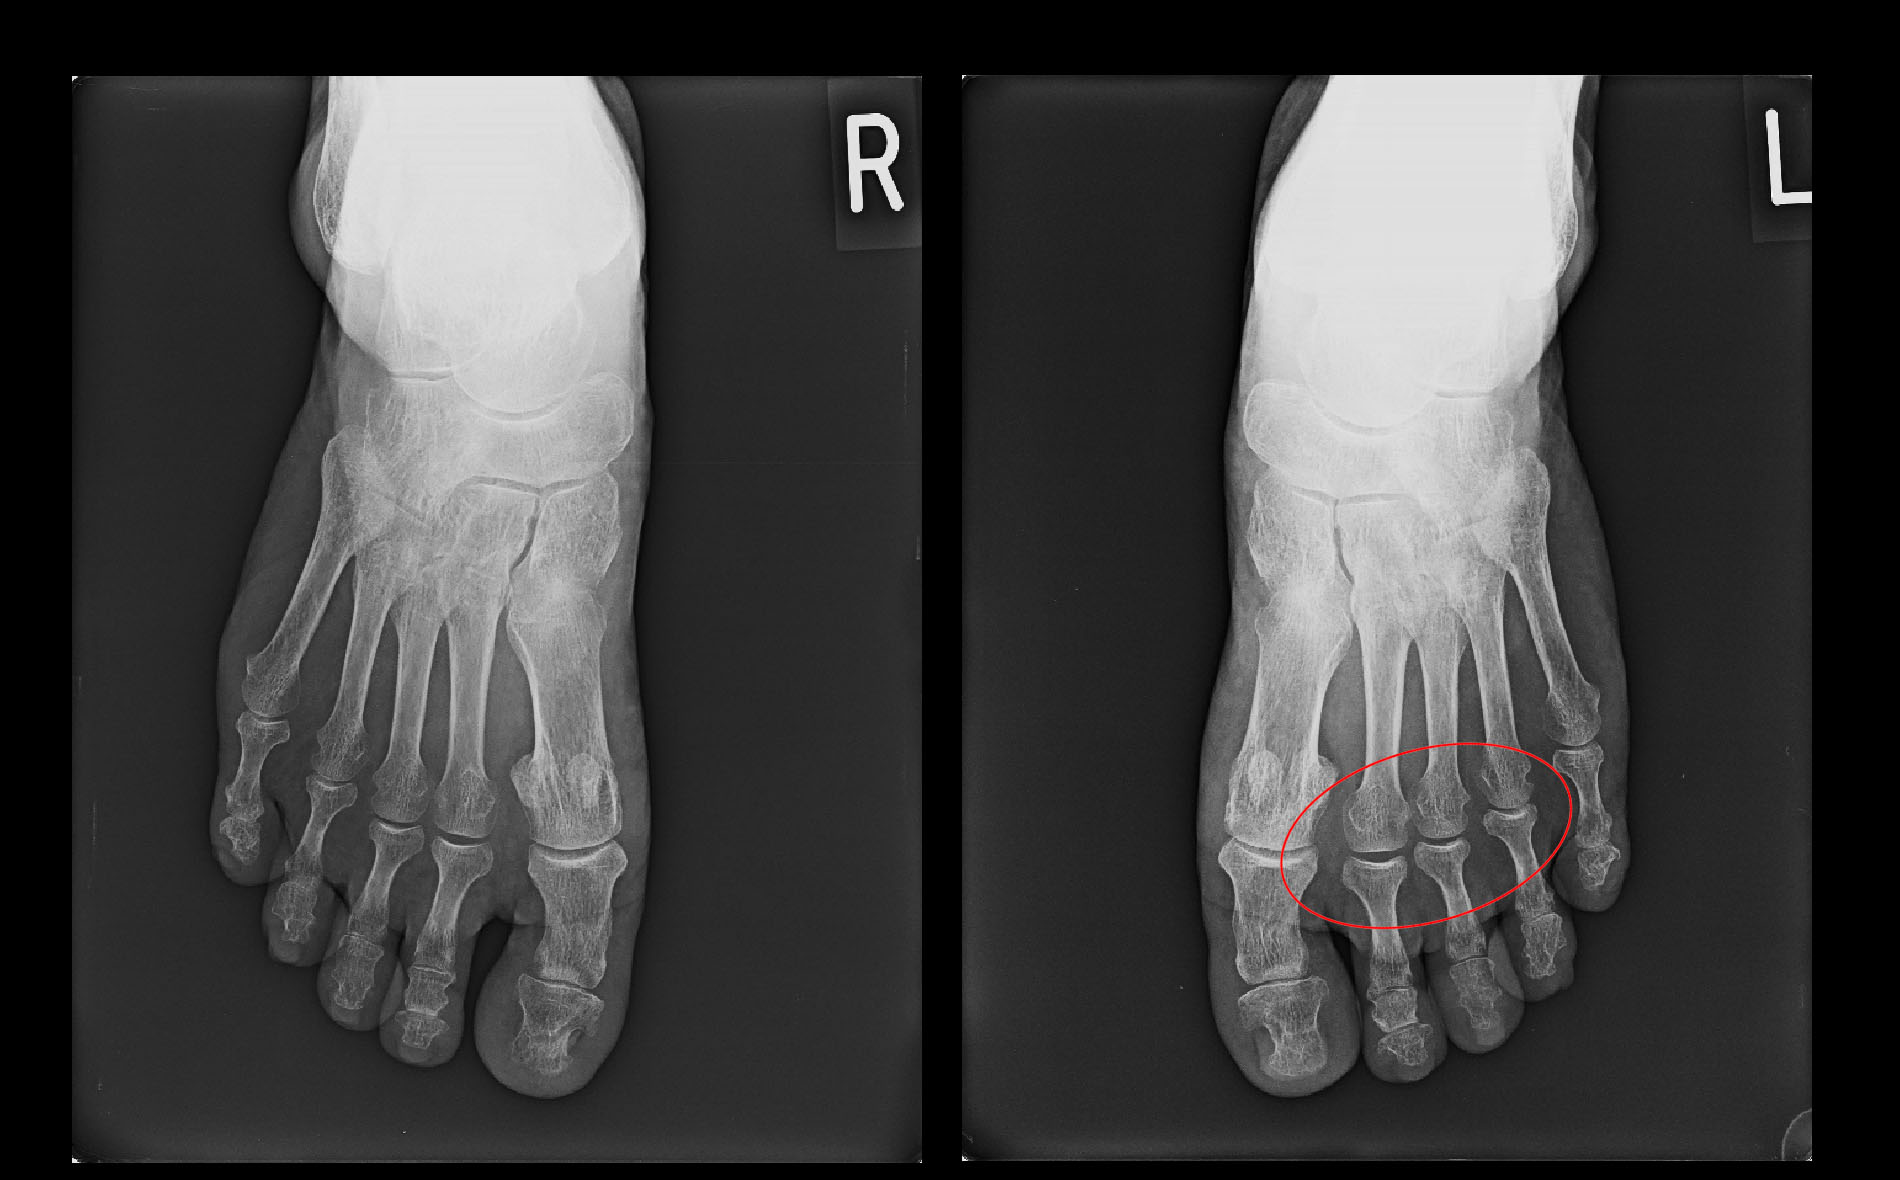

74才の女性で令和3年10月7日に1年前から左第1足指MP関節痛が続いているということで受診されました。内科で痛風の治療薬の処方を受けているということでした。足の第1足指MP関節痛は男性であれば痛風の可能性が極めて高いと判断しますが、女性でも時には痛風の方もいます。しかし、痛風の薬を服用し続けているのに症状は改善していないのですから、痛風の痛みではないはずです。

レントゲン像では左第1足指のMP関節は関節の隙間はかなり狭く、骨の端はとがっていて中等度~重度の変形性関節症の所見です。この患者さんにヒアルロン酸の関節内注入を施行してみました。

74才女 Xp1.jpg

1週後の10月14日にはVAS6の歩行痛は0となりました。2度目のヒアルロン酸の関節内注入は行いましたが、当初予定した5回の連続の注射は2回で終了となりました。